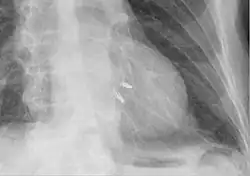

Chest radiograph showing two MitraClips projecting over the heart.